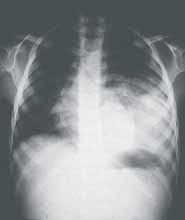

El único hallazgo al examen físico fue disminución de los ruidos respiratorios en el hemitórax izquierdo. No se le encontró ninguna otra malformación asociada. Los rayos X mostraron desplazamiento de la silueta cardiomediastínica hacia la derecha, con opacidad en base pulmonar izquierda y posterobasal en la proyección lateral (ver Figuras 1 y 2). (Ver: Factores asociados a complicaciones debidas a la realización de broncoscopias en pacientes pediátricos)

Figura 1. Radiografía de tórax proyección PA. Opacidad en base pulmonar izquierda y posterobasal. Secuestro intrapulmonar